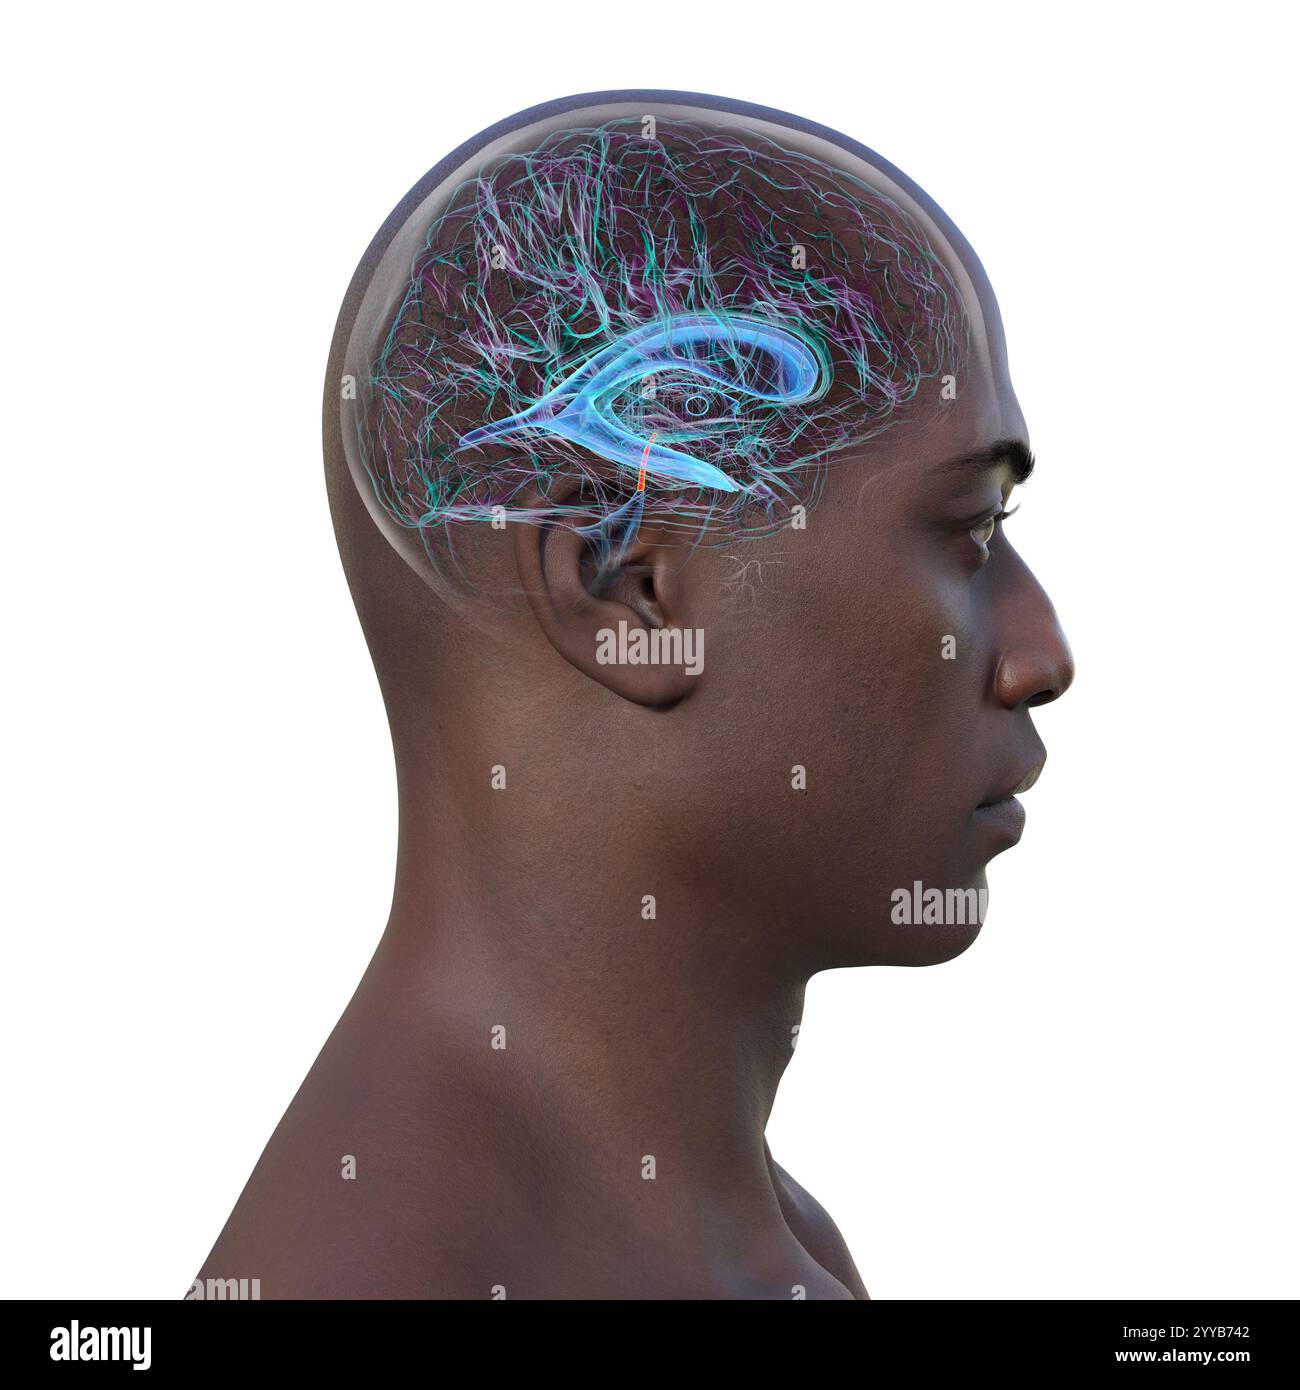

RF2T7NGWR–Ventrikel und Hirn-Aquädukt-Röntgenprofil Nahansicht 3D-Rendering-Illustration mit Körperkonturen. Anatomie des menschlichen Gehirns und des Ventrikelsystems,

RF2T030FH–Röntgenprofilansicht des Sylvius oder des zentralen Aquädukts des Gehirns 3D-Rendering-Illustration. Menschliche Körperanatomie, Medizin, Biologie, Wissenschaft, Neurowissenschaft,

RF2T6AR96–Röntgenprofil des Gehirns oder sylvius aquädukt Nahansicht 3D-Rendering-Illustration mit Körperkonturen. Anatomie des menschlichen Gehirns und des Ventrikelsystems, med